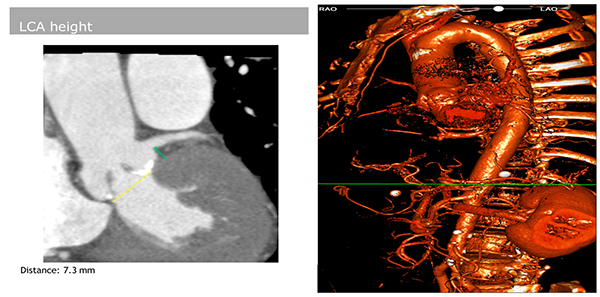

術前CT評估發現患者左側冠脈開口低(7.3mm)、瓣葉過長、冠脈風險過高,同時患者主動脈弓夾角小,輸送系統過弓風險極大。